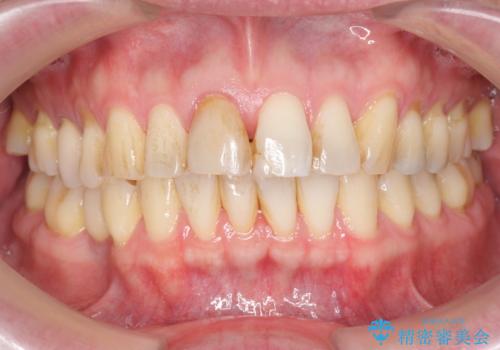

周囲の歯の色調に合わせた、自然なセラミック治療を行うことができましt。

セラミック治療の注意事項(リスク・副作用など)

- 天然歯を削ります

- 硬い素材は天然歯を傷つけてしまう場合があります

- かみ合わせや歯ぎしりが強すぎる方はセラミックが割れてしまう可能性があります

- 自費診療(保険適用外治療)となります